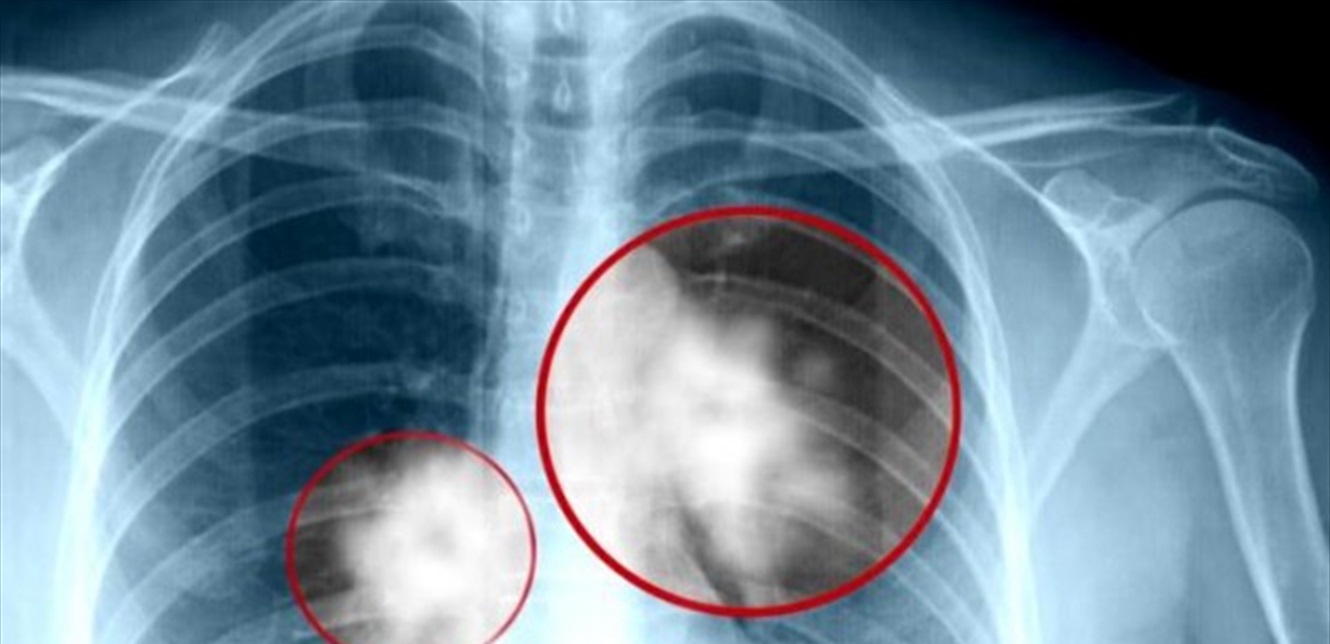

يبدأ سرطان الرئة بتكاثر الخلايا من أنسجة الرئة الطبيعية غير المنضبطة حتى تشكل كتلة ورم داخل الرئة، وتبدأ في النمو والتحرك من مكانها لتنتشر لاحقا إلى الأنسجة المحيطة أو إلى الأعضاء البعيدة كما نوضح لكم مراحل سرطان الرئة في السطور التالية.

يبدأ سرطان الرئة دون ظهور أعراض واضحة، ولكن هناك شكاوى متكررة من المريض تؤدي إلى التفكير في الإصابة بالسرطان مثل التهاب الشعب الهوائية المزمن لدى المدخنين، ومع إجراء الأشعة السينية أو الأشعة المقطعية يتم تشخيص الإصابة بسرطان الرئة عن طريق المصادفة.